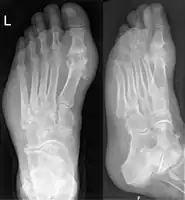

Gout may be diagnosed and treated without further investigations in someone with hyperuricemia and the classic acute arthritis of the base of the great toe (known as podagra). Synovial fluid analysis should be done if the diagnosis is in doubt.[15][45] Plain X-rays are usually normal and are not useful for confirming a diagnosis of early gout.[8] They may show signs of chronic gout such as bone erosion.[41]

Gout on X-rays of a left foot in the metatarsal-phalangeal joint of the big toe. Note also the soft tissue swelling at the lateral border of the foot. -